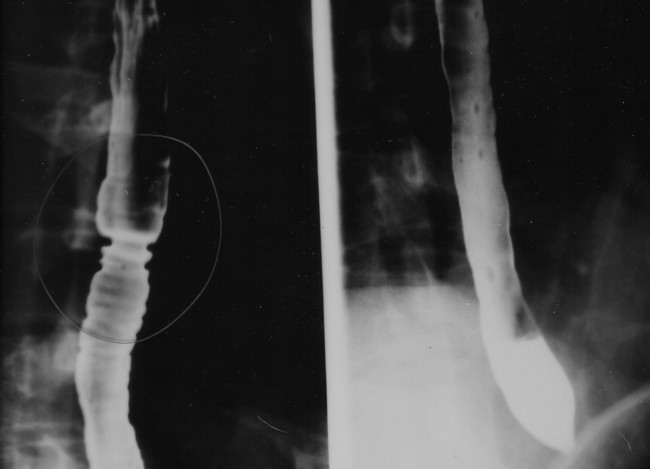

상부위장관조영술은 X선을 이용하여 식도, 위, 십이지장 등 상부 위장관의 외형과 기능을 검사하는 방법으로, 바륨 조영제를 사용하여 식도 역류, 궤양, 종양, 위장관 운동 이상 등을 진단하며, 바륨 삼킴 검사, 바륨 식사 검사 등 다양한 종류가 있다. - 바륨 - 바륨 동위 원소

황산바륨은 독성이 낮고 약 4.5 g/cm3의 비교적 높은 밀도(따라서 X선에 대한 불투명도)를 가지고 있다. 이러한 이유로 소화기계의 X선 영상에서 조영제로 사용된다("바륨 밀" 및 "바륨 관장").[2] 리토폰은 황화물에 노출되어도 어두워지지 않는 우수한 피복력을 가진 영구 백색 안료이다.[20]